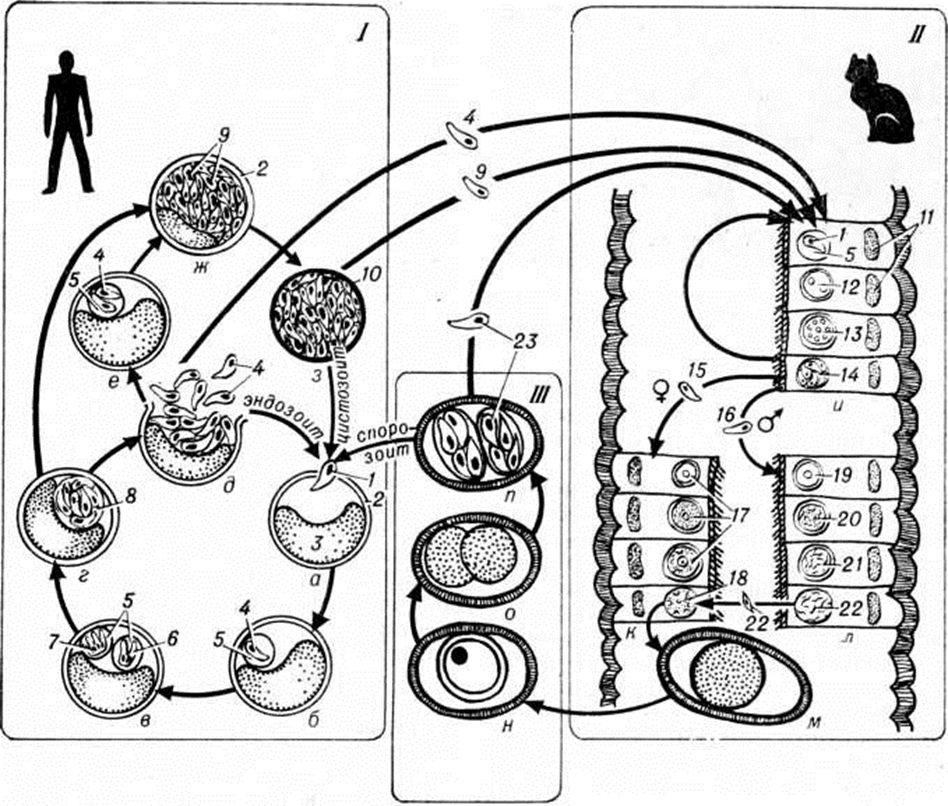

ТоксоплазмозТоксоплазмоз (toxoplasmosis) — паразитарная болезнь, вызываемая простейшими и характеризующаяся поражением нервной и лимфатической систем, глаз, скелетных мышц, миокарда и другие Различают приобретённый и врождённый Токсоплазмоз Возбудитель токсоплазмоза Toxoplasma gondii открыт в 1908 год французский исследователями Ш. Николлем и Мансо (L. Manceaux), обнаружившими его в Тунисе у грызунов Ctenodactyluo gundi, и итал. исследователем Сплендоре (A. Splendore), выявившим его в Бразилии у кроликов. На территории СССР токсоплазмы впервые были выделены от сусликов Н. А. Гайским и Д. Н. Засухиным в 1930 год В 1923 год чешский исследователь Янку (3. Jankii) обнаружил токсоплазмы в глазу умершего ребенка, доказав тем самым восприимчивость людей к заражению этим паразитом. Первый случай врождённого Токсоплазмоз человека описали Вольф (A. Wolf), Кауэн (D. Cowen) и Пейдж (P. Paige) в 1939 год Важной вехой в изучении Токсоплазмоз была разработка методов его иммунодиагностики. Оригинальную серологическую реакцию с красителем предложили в 1948 год Сейбин (А. В. Sabin) и Фельдман (Н. A. Feldman) — реакция Сейбина — Фельдмана (РСФ). Кожную пробу с токсоплазмином предложил в том же году Френкель (J. К. Frenkel). В 1953 год Айлс (D. Eyles) и Коулмен (N. Coleman) ввели в практику лечения Токсоплазмоз дараприм (хлоридин) в комбинации с сульфаниламидами. Систематическое положение Toxoplasma gondii оставалось неопределенным до открытия Хатчисоном (W. М. Hutchison) в 1969 год половой фазы развития паразита, которая протекает в кишечнике представителей семейства кошачьих. Этиология. Возбудитель Токсоплазмоз— облигатный внутриклеточный паразит Toxoplasma gondii, отряда Eucoccidiida, типа Apicomplexa, относится к тканевым цистообразующим кокцидиям. Наименование рода Toxoplasma (греческий toxon лук, арка, дуга + plasma вылепленное, оформленное) определяется формой паразита (в виде полумесяца). Развитие токсоплазм происходит со сменой хозяев. Окончательные хозяева токсоплазм — кошка и некоторые другие представители кошачьих, промежуточные — млекопитающие (кроме кошачьих), дикие животные (свиньи, овцы и другие), человек и птицы. В процессе развития токсоплазм установлены следующие фазы: внекишечная тканевая фаза — бесполое размножение токсоплазм (эндодиогения и эндополигения) в различных тканях промежуточных хозяев; кишечная фаза — бесполое размножение (шизогония) и половое размножение (гаметогония) токсоплазм в клетках эпителия слизистой оболочки кишечника окончательных хозяев; фаза спорогонии, которая начинается в просвете кишечника окончательных хозяев и заканчивается в окружающей среде (рисунок 1). Промежуточные хозяева, в том числе и человек, могут заражаться либо спорозоитами из спорулированных ооцист, попавших в почву с фекалиями кошек (или с рук, пола, мебели, предметов обихода, загрязнённых фекалиями кошек), либо цистозоитами из цист, содержащимися в тканях других промежуточных хозяев (в частности, при употреблении людьми в пищу недостаточно термически обработанного мяса); либо эндозоитами, также содержащимися в тканях промежуточных хозяев (проникновение через поврежденную кожу при обработке тушек инвазированных животных). В организме человека (промежуточного хозяина), спорозоиты, эндозоиты и цистозоиты активно проникают в клетки (рисунок 1, I, а, б; рисунок 2) различных тканей и органов, где проходит бесполое развитие. Оно заключается в размножении их путём эндодиогении — внутреннего почкования (рисунок 1, I, в), в результате чего образуются две дочерние клетки (рисунок 1, I в, 6 рисунок 3), и эндополигении, при которой образуется четыре и более дочерних особей (рисунок 1, I в, 7). Ритм размножения эндозоитов определяется продолжительностью развития одного поколения токсоплазм и может быть быстрым (3—5 час) при остром течении Токсоплазмоз либо замедленным (10—15 часов и более) при хроническом Токсоплазмоз При остром течении инвазии в результате повторных делений эндозоитов образуются псевдоцисты (рисунок 1, I г, 8) — скопления эндозоитов одной генерации, окружённые оболочкой паразитофорной вакуоли, сформированной клеткой хозяина. Поражённая клетка, переполненная эндозоитами разрушается (рисунок 1, I д), эндозоиты активно внедряются в соседние клетки, где вновь начинается бесполое развитие (рисунок 1, I а—д). При хроническом Токсоплазмоз медленный темп размножения эндозоитов (рисунок 1, I е) приводит к образованию цистозоитов (рисунок 1, I ж), находящихся внутри цист и продолжающих медленно размножаться (рисунок 1, I з). |

Окончательные хозяева (кошки) могут также заражаться токсоплазмами, находящимися на разных стадиях развития,— спорозоитами, цистозоитами, эндозоитами (рисунок 1, 17), что определяет продолжительность периода от момента заражения до начала выделения ооцист в окружающую среду: при заражении спорозоитами — 20 дней и более, цистозоитами — 3—10 дней, эндозоитами — 19 дней. Развитие токсоплазм в клетках эпителия слизистой оболочки кишечника кошки начинается с процесса шизогонии (рисунок 1, 17, г). При этом образуется несколько морфологически различных типов мерозоитов, одни из которых являются так называемый предшественниками следующих за ними половых стадий женских (рисунок 1, II, 15) и мужских (рисунок 1, II, 16) гаметоцитов. Половое развитие токсоплазм в организме кошки начинается с образования макрогаметоцитов (рисунок 1, II, к, 17) и микрогаметоцитов (рисунок 1, II, л, 19—21). Их развитие приводит к формированию макрогамет (рисунок 1, II, к, 18) и микрогамет (рисунок 1, II, 22). Микрогаметы проникают в зрелую макрогамету и в результате оплодотворения формируется ооциста (рисунок 1, II, м). Ооциста разрушает эпителиальную клетку кишечника окончательного хозяина (кошки) и выходит в его просвет, а затем с фекалиями — в окружающую среду (рисунок 1, III, н) (в почву, в воду, на растения), попадает на предметы обихода, руки. При благоприятных условиях аэрации и температурного режима в течение 2—5 дней происходит созревание ооцисты и образование внутри неё двух спороцист (рисунок 1, III, о), а затем в каждой спороцисте — четырех спорозоитов (рисунок 1, III, п).